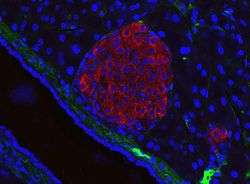

Pancreatic islet (mouse) in its typical proximity to a blood vessel; insulin in red, nuclei in blue. | |

The pancreatic islets or islets of Langerhans are the regions of the pancreas that contain its endocrine (i.e., hormone-producing) cells, discovered in 1869 by German pathological anatomist Paul Langerhans.[2] New studies show that the pancreatic islets constitute approximately 4.5% of the pancreas volume[1] and receive 10-15% of its blood flow.[3] The islets of Langerhans are arranged in density routes throughout the healthy human pancreas.[1]

There are about 3 million islets distributed in the form of density routes throughout the pancreas of a healthy adult human,[1] each of which measures an average of about 0.1 mm (109 µm) in diameter.[1][4]:914 Each is separated from the surrounding pancreatic tissue by a thin fibrous connective tissue capsule which is continuous with the fibrous connective tissue that is interwoven throughout the rest of the pancreas.[4]:914 The combined mass of the islets is 2 grams.[1] Islets of Langerhans can also form super structures called Islet clusters which are composed of small islets that surround large blood vessels.[1] The roundness of islets along the pancreas has also been quantified through the Index of Sphericity method.[1] Thus, the islets closest to the spherical form are mainly found in the pancreas tail whereas the islets farthest from the spherical form are found in the pancreas neck.[1]